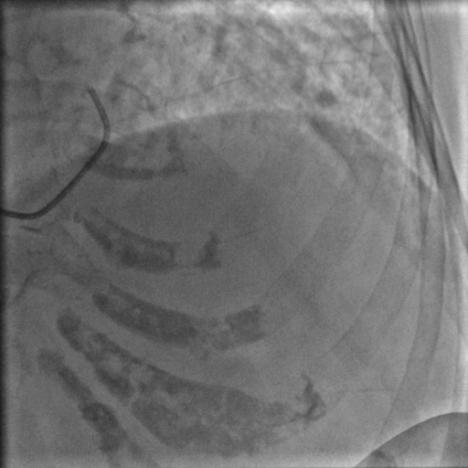

常规消毒、铺巾,再穿刺、放鞘管、送入造影导管、造影,一切顺利,造影结果如下:

图2

图3

图4

比我们想象中的要好,前降支中段闭塞,第一、第二对角支都还在,回旋支、右冠都还好,可以稍微松一口气。